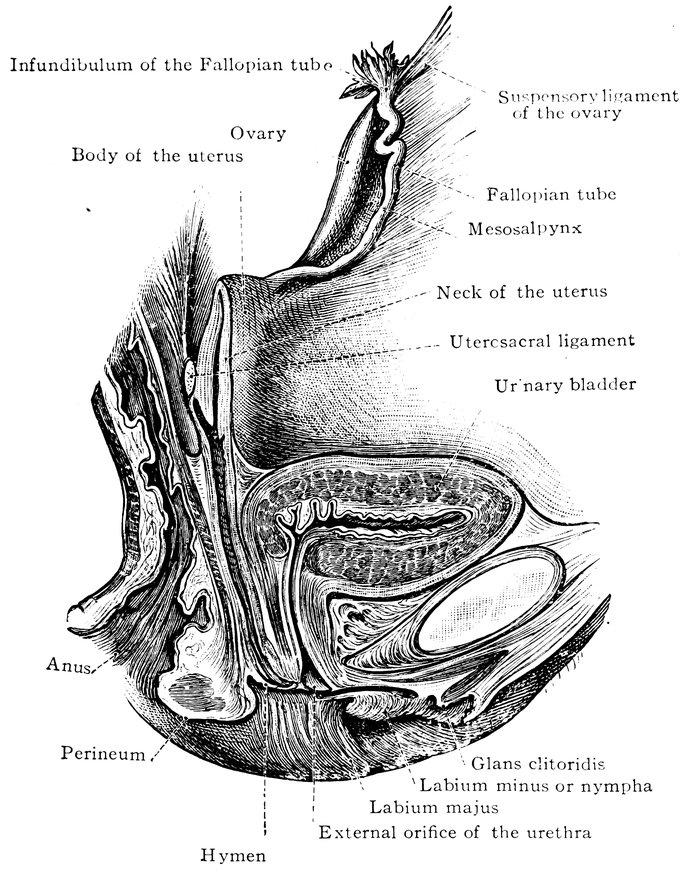

| 2. | Portion of the pelvic viscera in the female, etc. | 9 |

| 14. | Sagittal section of the female pelvis | 56 |

| 48. | The female pudendum, or vulva, with the labia majora | 204 |

| 49. | Vestibule of the vagina, with the labia minora or nymphæ, etc | 205 |

| 50. | The uterus, the left Fallopian tube and the left ovary, etc | 207 |

| 51. | Female internal genital organs in the fully developed state | 208 |